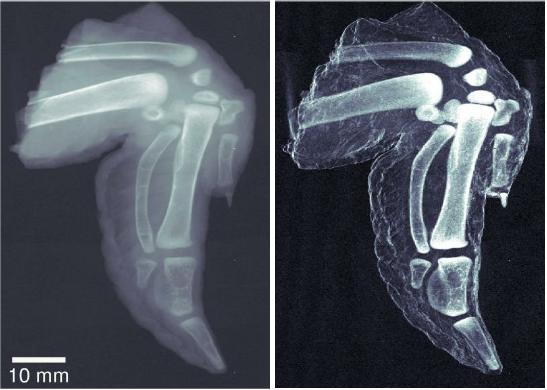

Unlike traditional x-ray images, which show a simple absorption contrast, dark-field images capture the scattering of the radiation within the material itself, exposing subtle inner changes in bone, soft tissue, or alloys. The overall clarity of the images is striking. The improved sensitivity in measuring bone density and hairline fractures could help diagnose the onset of osteoporosis. Because cancer or plaque cells scatter radiation slightly differently than normal cells, dark-field x-ray images can also be used to explore soft tissue, providing safer early diagnosis of breast cancer or the plaques associated with Alzheimer’s disease.

Hard-x-ray dark-field imaging using a grating interferometer, by F. Pfeiffer et al, Nature Materials, January 20, 2008.